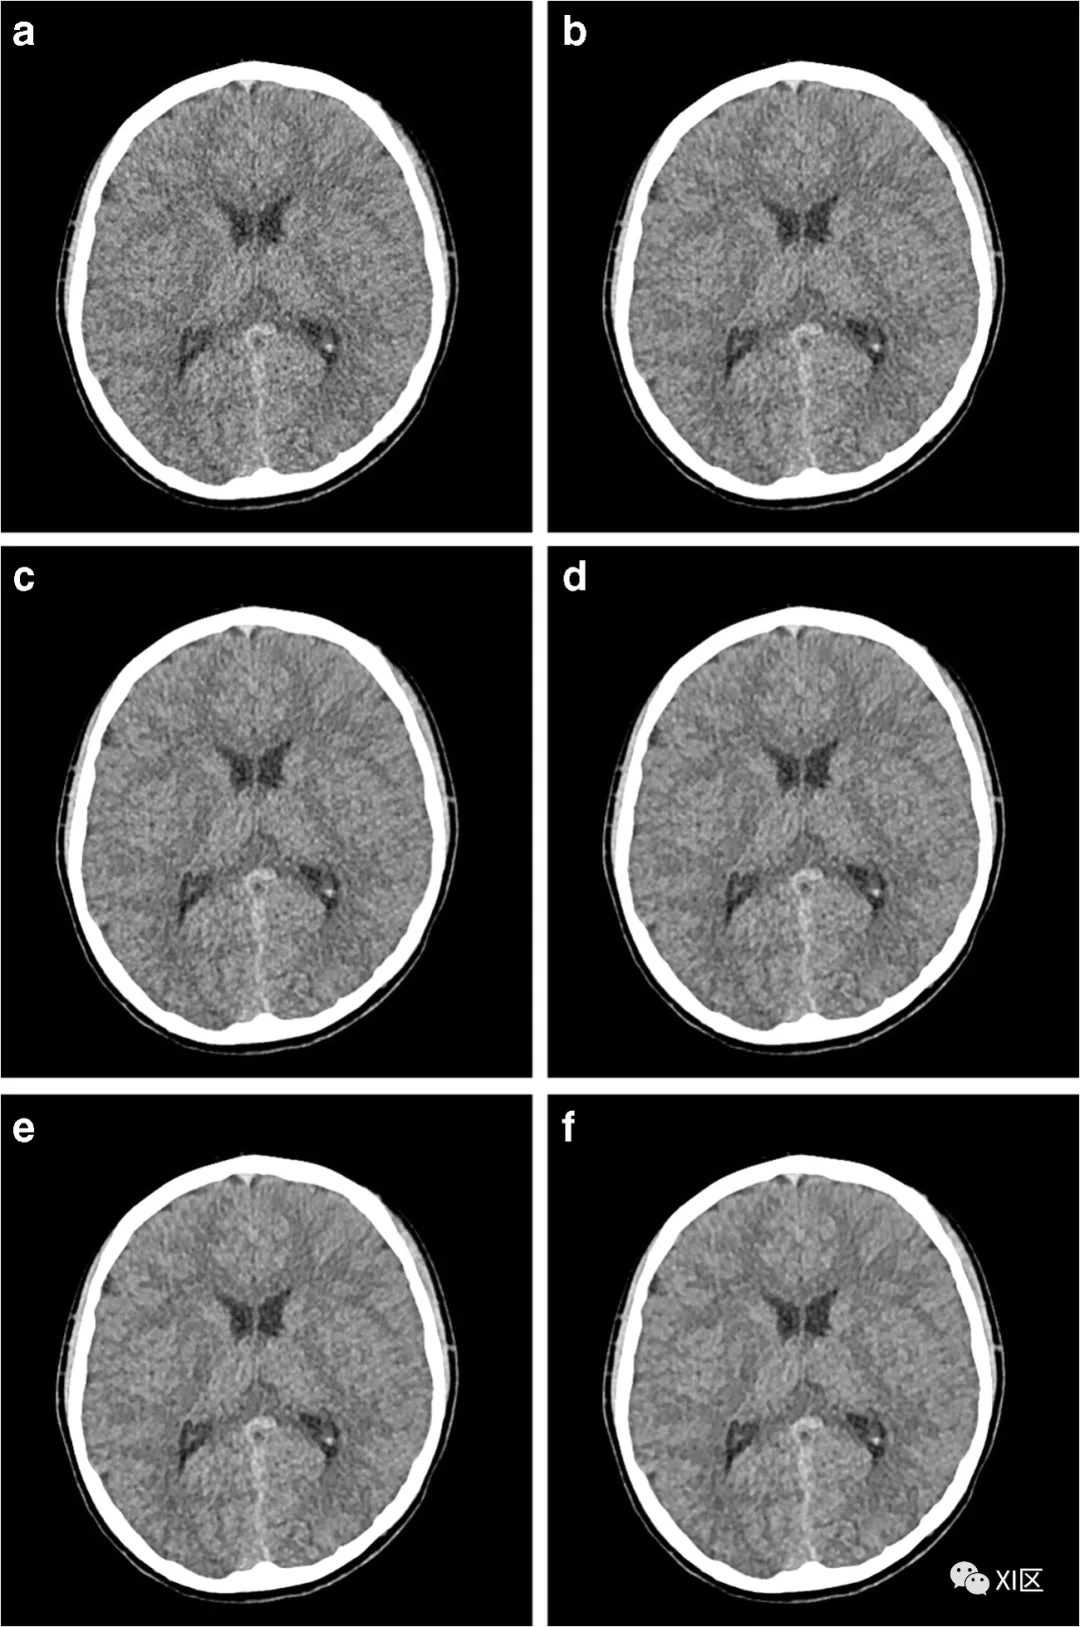

迭代重建本身并不能降低辐射剂量,但是使用迭代重建后,图像质量可以有很好的改善,再次基础上,可以使用更低的条件进行扫描,从而降低辐射剂量。研究发现,使用ADMIRE在降低剂量的儿童头颅扫描中,可以改善主观和客观的图像质量。

6岁女性,头部外伤。低剂量侧脑室水平CT图像(110kV,55mAs)。a-f分别为滤波反投影及strengths1-5ADMIRE重建CT图像比较。

ChoHH,LeeSM,nstruction:focusonimagequalityandreductionofradiationdose[J].PediatricRadiology,2020,50(2).